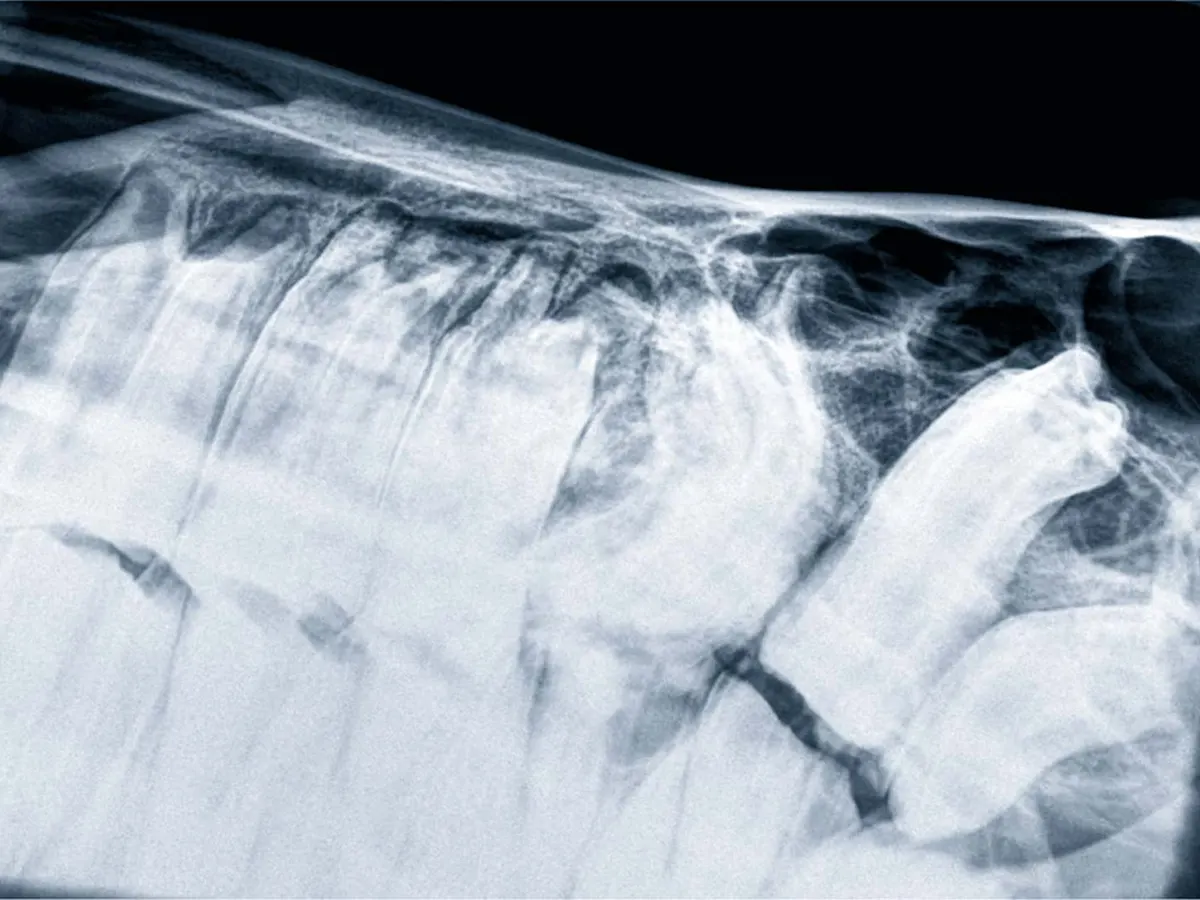

Rendgenske snimke su neinvazivan način za uvid u nutrinu naših ljubimaca.

Dvije glavne vrste tkiva u koje dobivamo uvid pomoću rendgenskog snimanja su kosti i strukture mekog tkiva.

Pomoću rendgena, između ostaloga, možemo dijagnosticirati:

Rendgenskim pregledima se također mogu pratiti zarastanja prijeloma, promatranje uspješnosti ortopedskih operacija ili rast kostiju kod mladih životinja.